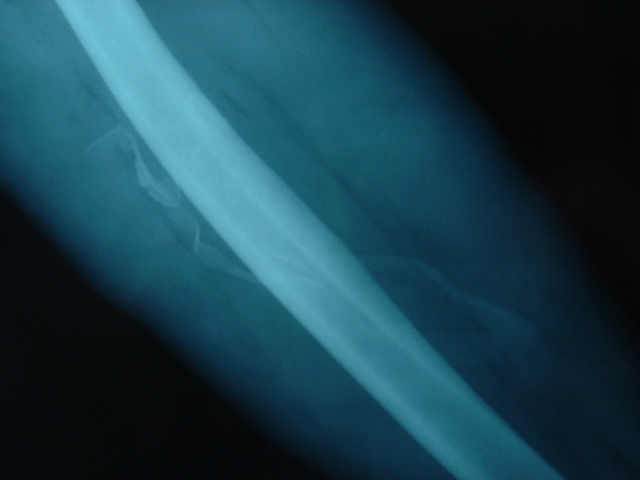

A Rx. se ven perfectamente los drenajes y se puede calibrar la longitud.